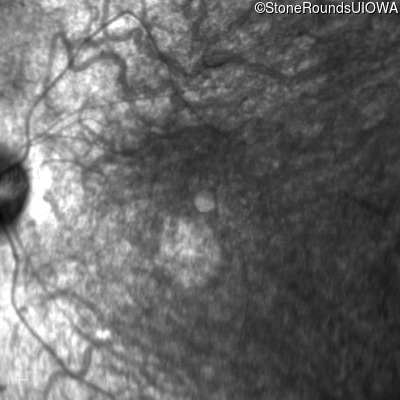

Infrared Fundus Photograph - Right - 5/180

Exemplar

Infrared Fundus Photograph - Left - 5/225